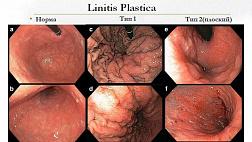

- Атлас